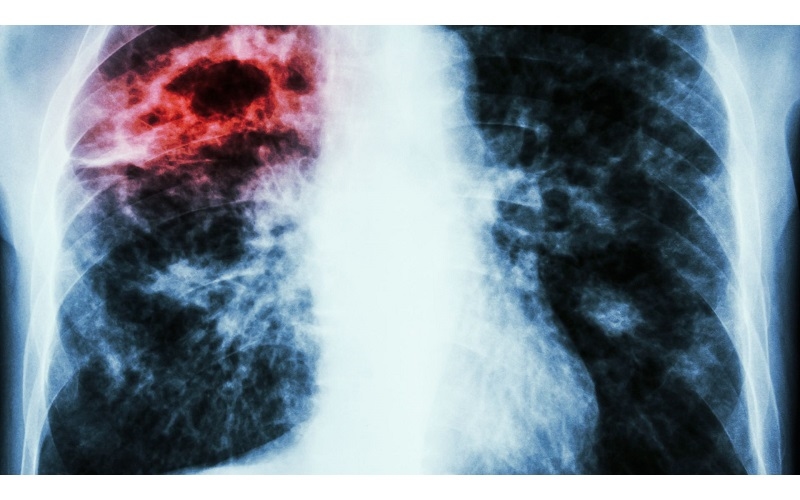

Nhận biết biểu hiện lâm sàng của áp xe phổi

Áp xe phổi là tình trạng nhiễm trùng nghiêm trọng, xảy ra khi mô phổi bị hoại tử và hình thành các ổ mủ sâu bên trong nhu mô phổi. Bệnh có thể tiến triển âm thầm nhưng cũng có lúc bùng phát dữ dội, đe dọa tính mạng nếu không điều trị kịp thời. Do đó, nhận biết biểu hiện lâm sàng của áp xe phổi là điều cực kỳ quan trọng giúp người bệnh và nhân viên y tế chủ động chẩn đoán sớm, tránh nhầm lẫn với các bệnh lý hô hấp khác như viêm phổi hay lao phổi.